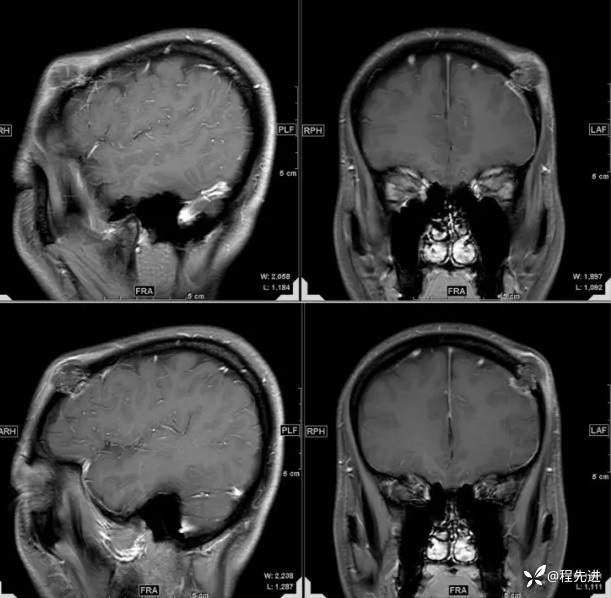

【患者信息】:女,31岁

【主诉】:发现头部肿物1月余

【现病史及既往史】:患者自诉于1月前无明显诱因出现左额颞部肿块,大小约3*3cm,伴疼痛红肿发热,遂至我院外科门诊就诊考虑“局部感染”,予以对症治疗后,肿块疼痛红肿好转,但肿块无明显缩小。

【检查】:常规检验项目均(-)